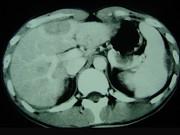

问题 男,35岁,病人低热、消瘦、乏力,左右季肋区疼痛,CT扫描如图,请选择最佳诊断()

选项 A.肝脓肿、腹腔脓肿 B.肝结核、腹腔结核 C.肝癌、腹腔转移 D.肝脏及腹腔转移瘤 E.肝海绵状血管瘤、腹腔脓肿

答案 B